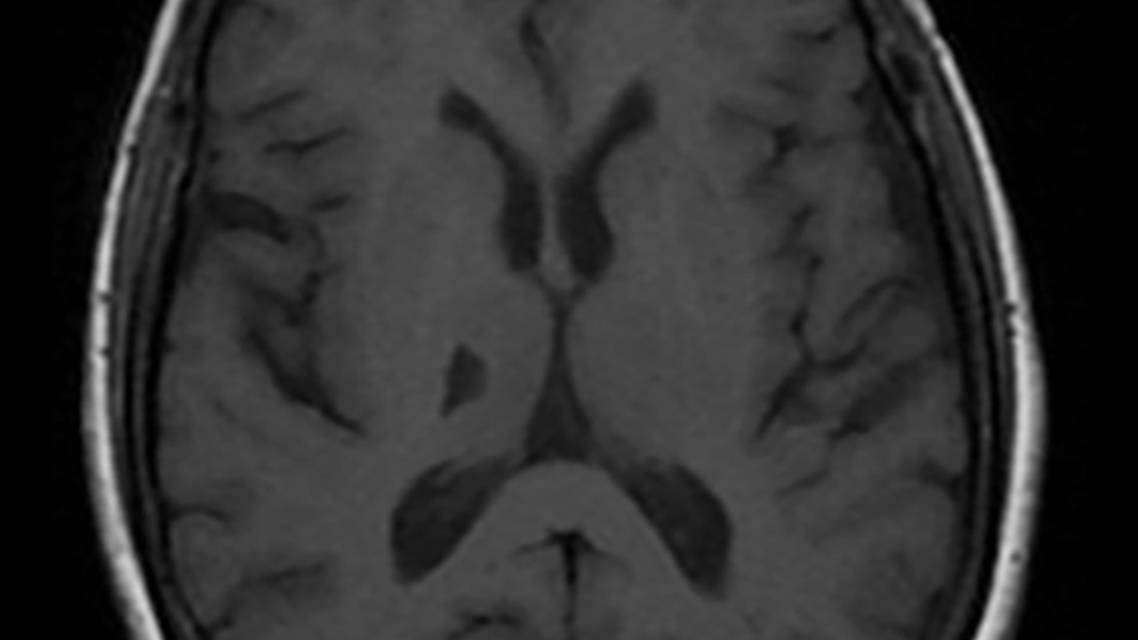

In individuals with adult-onset task-specific dystonia, no further diagnostic workup is needed. Brain MRI should be performed in all cases of early-onset dystonia, in combined forms, and when a lesion is suspected. Iron-sensitive sequences should be obtained to rule out neurodegeneration with brain iron accumulation (Figure 3). MRI can also be used to identify calcium accumulation (Figure 4), manganese accumulation (Figure 5), and structural causes such as pulvinar stroke (Figure 6).

Figure 6. MRI features of pulvinar stroke. Right thalamic hypointensity is seen on the T1-weighted image.